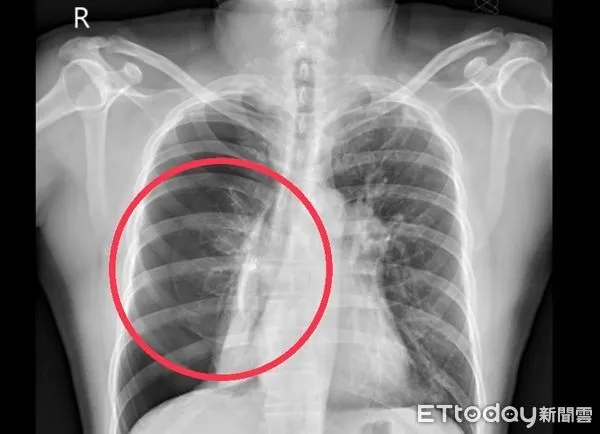

▲X光片的紅圈處顯示患者右肺明顯塌陷。(圖/衛福部南投醫院提供)

年約60歲的許姓男子月前某天午睡起來後,突然出現胸痛、無法深呼吸等症狀,相當難受,趕緊至急診室就醫,安排胸部X光檢查,發現右側肺部有氣胸,插上胸管將空氣引流、改善症狀;沒想到幾天後同側氣胸再次發作,送醫經醫師評估後,透過胸腔鏡肺楔狀切除手術,恢復順暢呼吸,也降低復發機率。